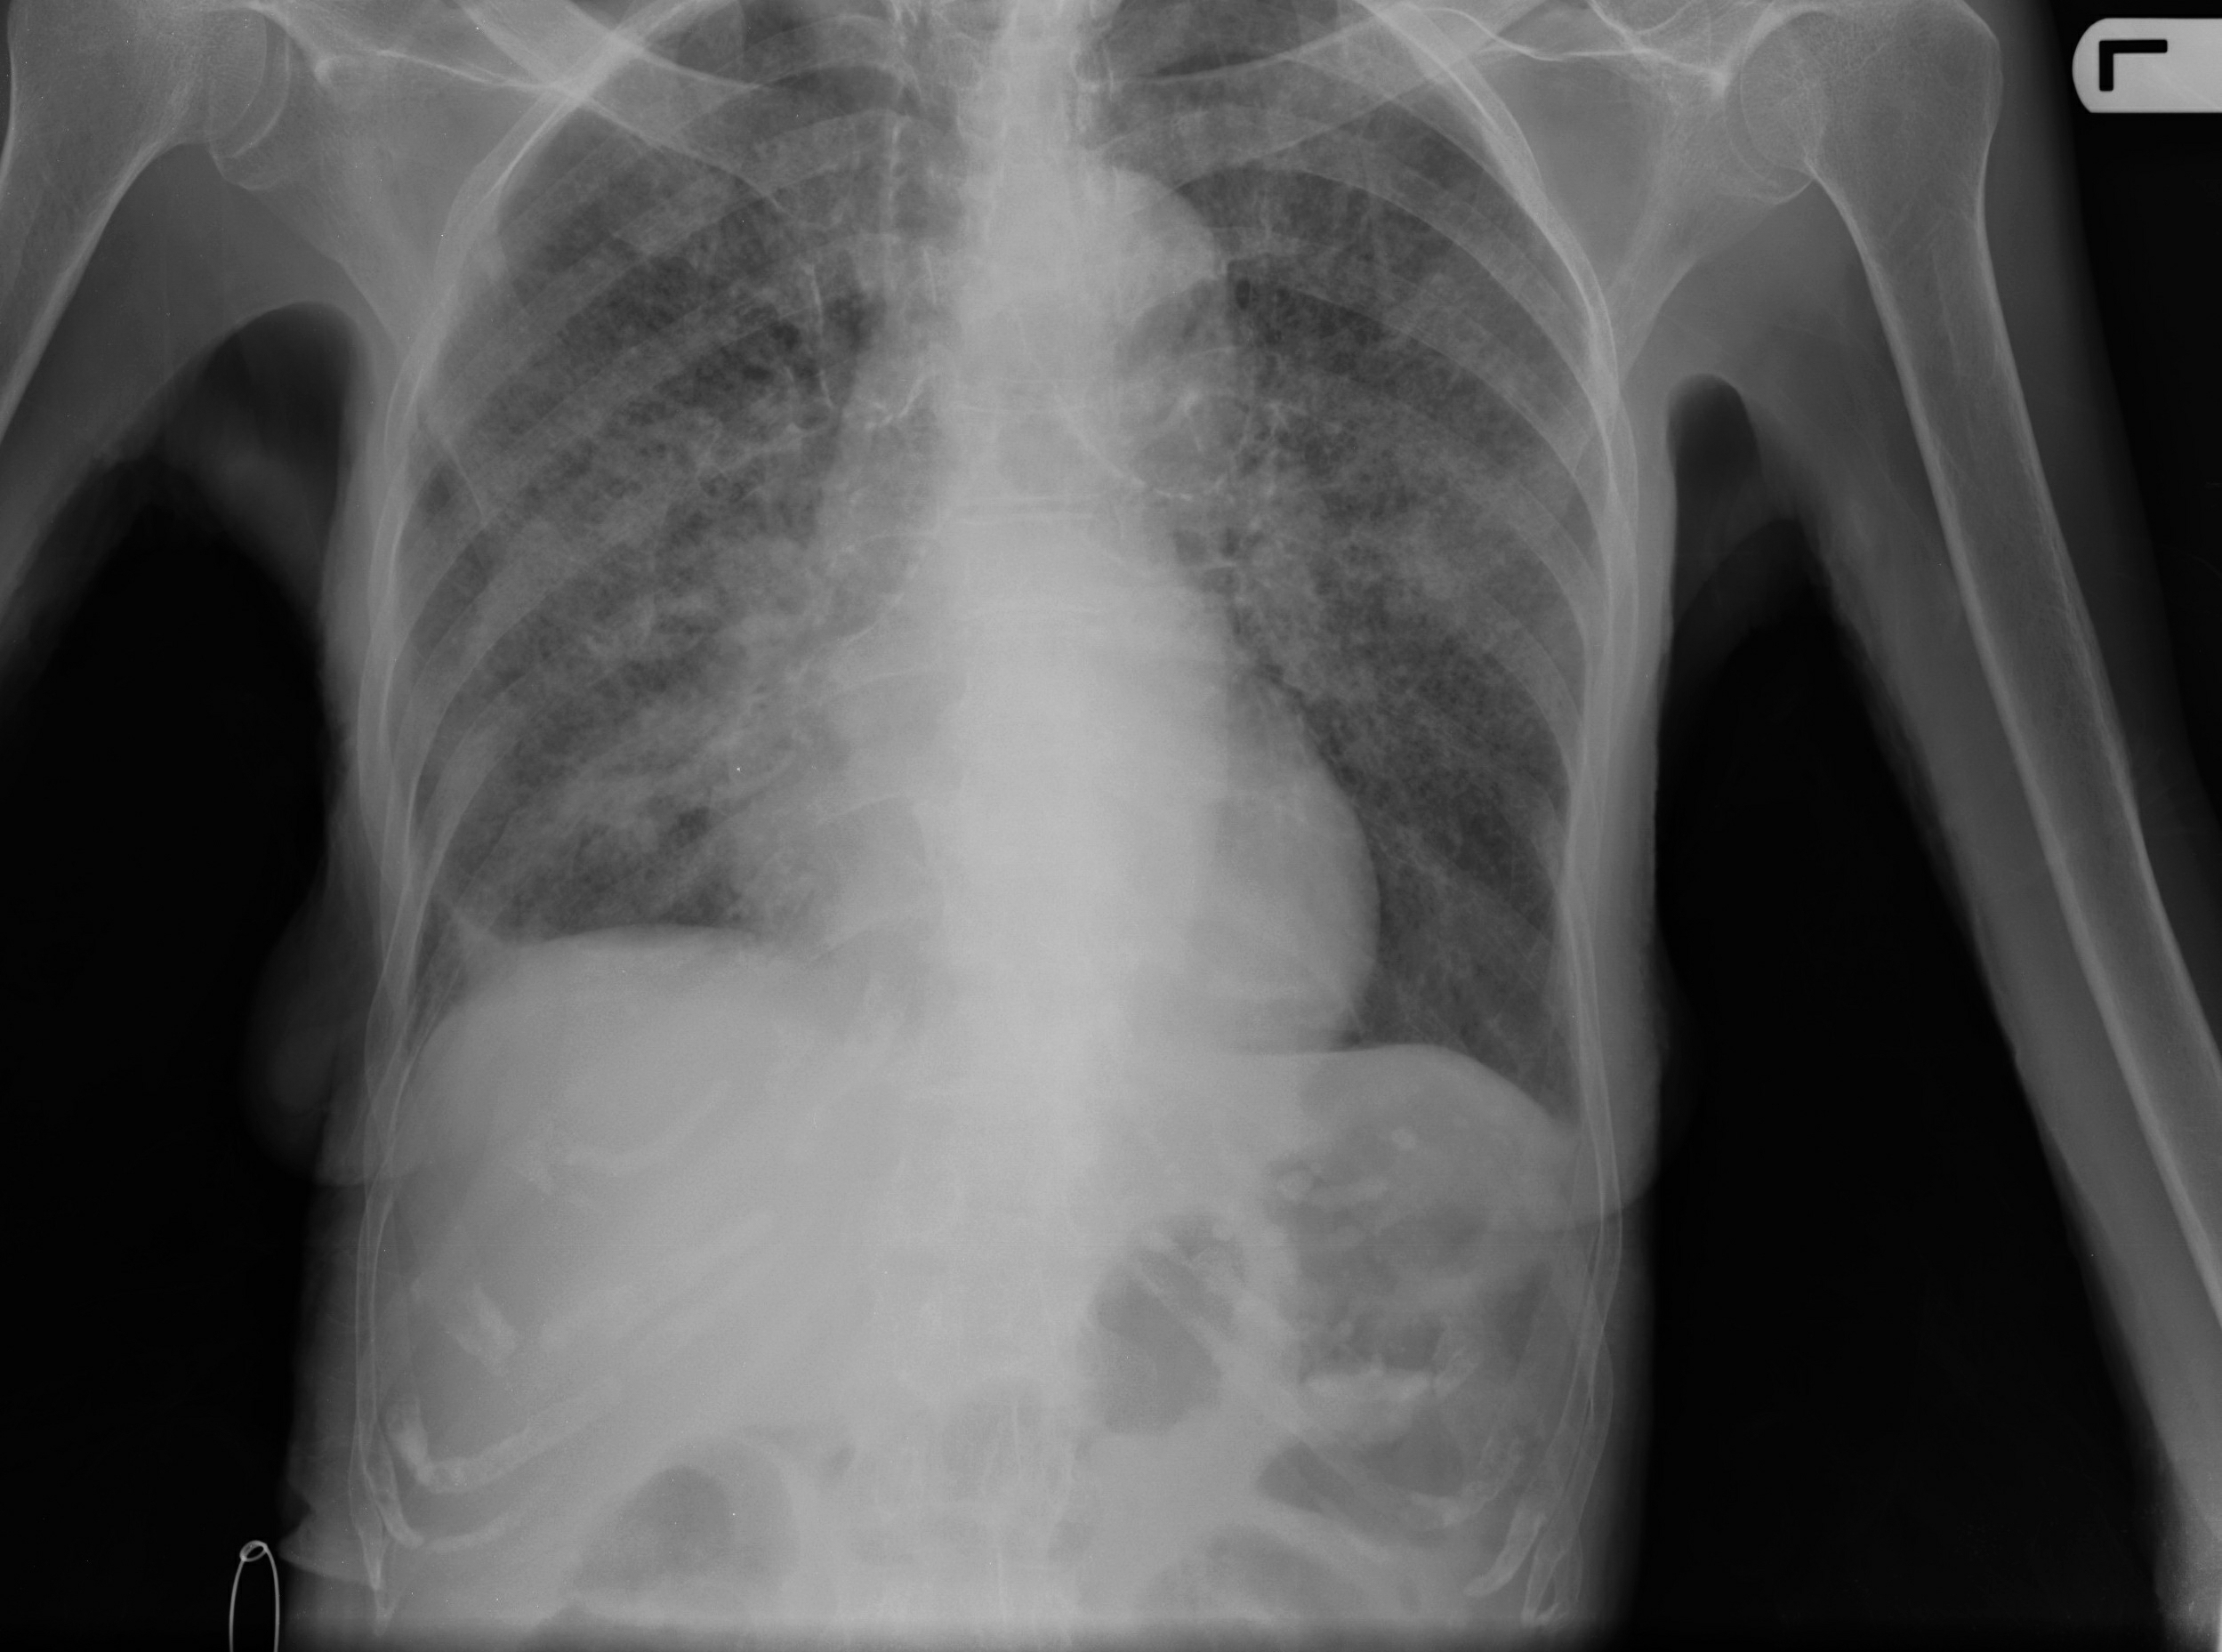

Обратиться к врачу нужно как можно быстрее, если у человека появилась одышка в состоянии покоя, боль в груди, синюшность губ, кашель с примесью крови. Симптомы могут указывать на пневмонию, ХОБЛ или тромбоэмболию легочной артерии. Без помощи специалиста проблему не решить.

Фото: Miliary tuberculosis, Yale Rosen from USA, Creative Commons Attribution-Share Alike 2.0 Generic license.